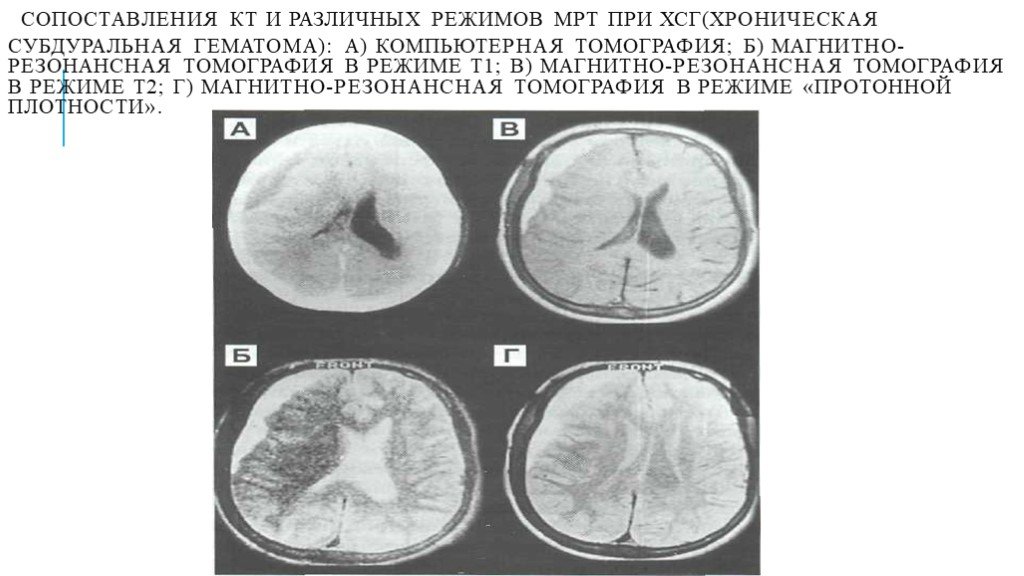

Компьютерная томография в неврологии презентация - 86 фото